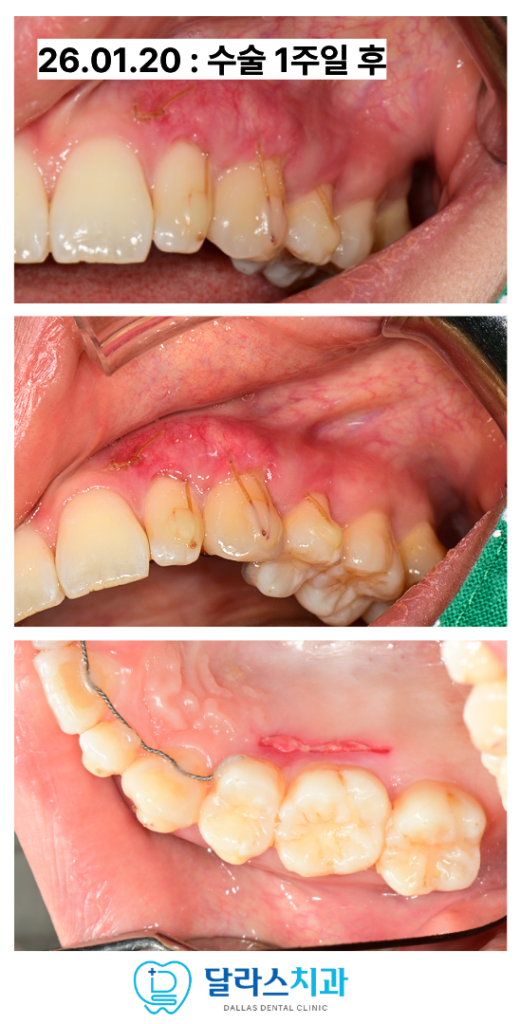

“수술 후 회복 과정은?”

환자분께서는 수술 초기에는 일상생활 속에서

장치를 꾸준히 착용하셨으며

어느 정도 초기 치유가 이루어진 후부터는 실밥을 제거하기 전까지

식사 시에만 장치를 착용하여 수술 부위를 보호하셨습니다.

이러한 세심한 사후 관리 덕분에 환자분께서는

우려했던 것보다 훨씬 편안하게 회복 과정을 거치실 수 있었습니다.

수술 후 3주가 지난시점에 잇몸이 아문 상태를 확인한 뒤

실밥을 깔끔하게 제거해드렸습니다.